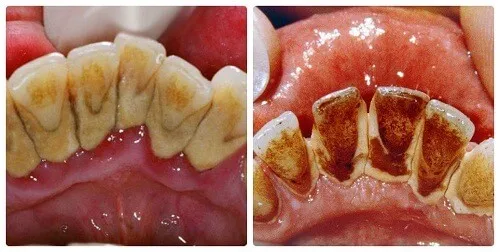

Cao răng là những mảng bám bám chặt vững chắc vào bề mặt răng theo thời gian. Tuy nhiên, nhiều người vẫn còn chủ quan việc chăm

Cao răng bị vỡ là hiện tượng khá phổ biến, nhưng không phải ai cũng biết cách xử lý đúng cách khi gặp phải tình trạng này.